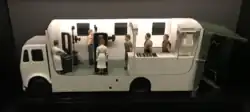

In many countries, miniature mass radiographs (MMR) was quickly adopted and extensively utilized in the 1950s. For example, in Brazil and in Japan, tuberculosis prevention laws went into effect, obligating ca. 60% of the population to undergo MMR screening. A model of a mass radiograph used for screening for tuberculosis from 1936 to the mid 1950s can be seen in the Medical Gallery of the Science Museum.[1] As a mass screening program for low-risk populations, the procedure was largely discontinued in the 1970s, following recommendation of the World Health Organization, due to three main reasons:

- ^ "Model of a mobile mass miniature x-ray unit". Science Museum Group Collection.